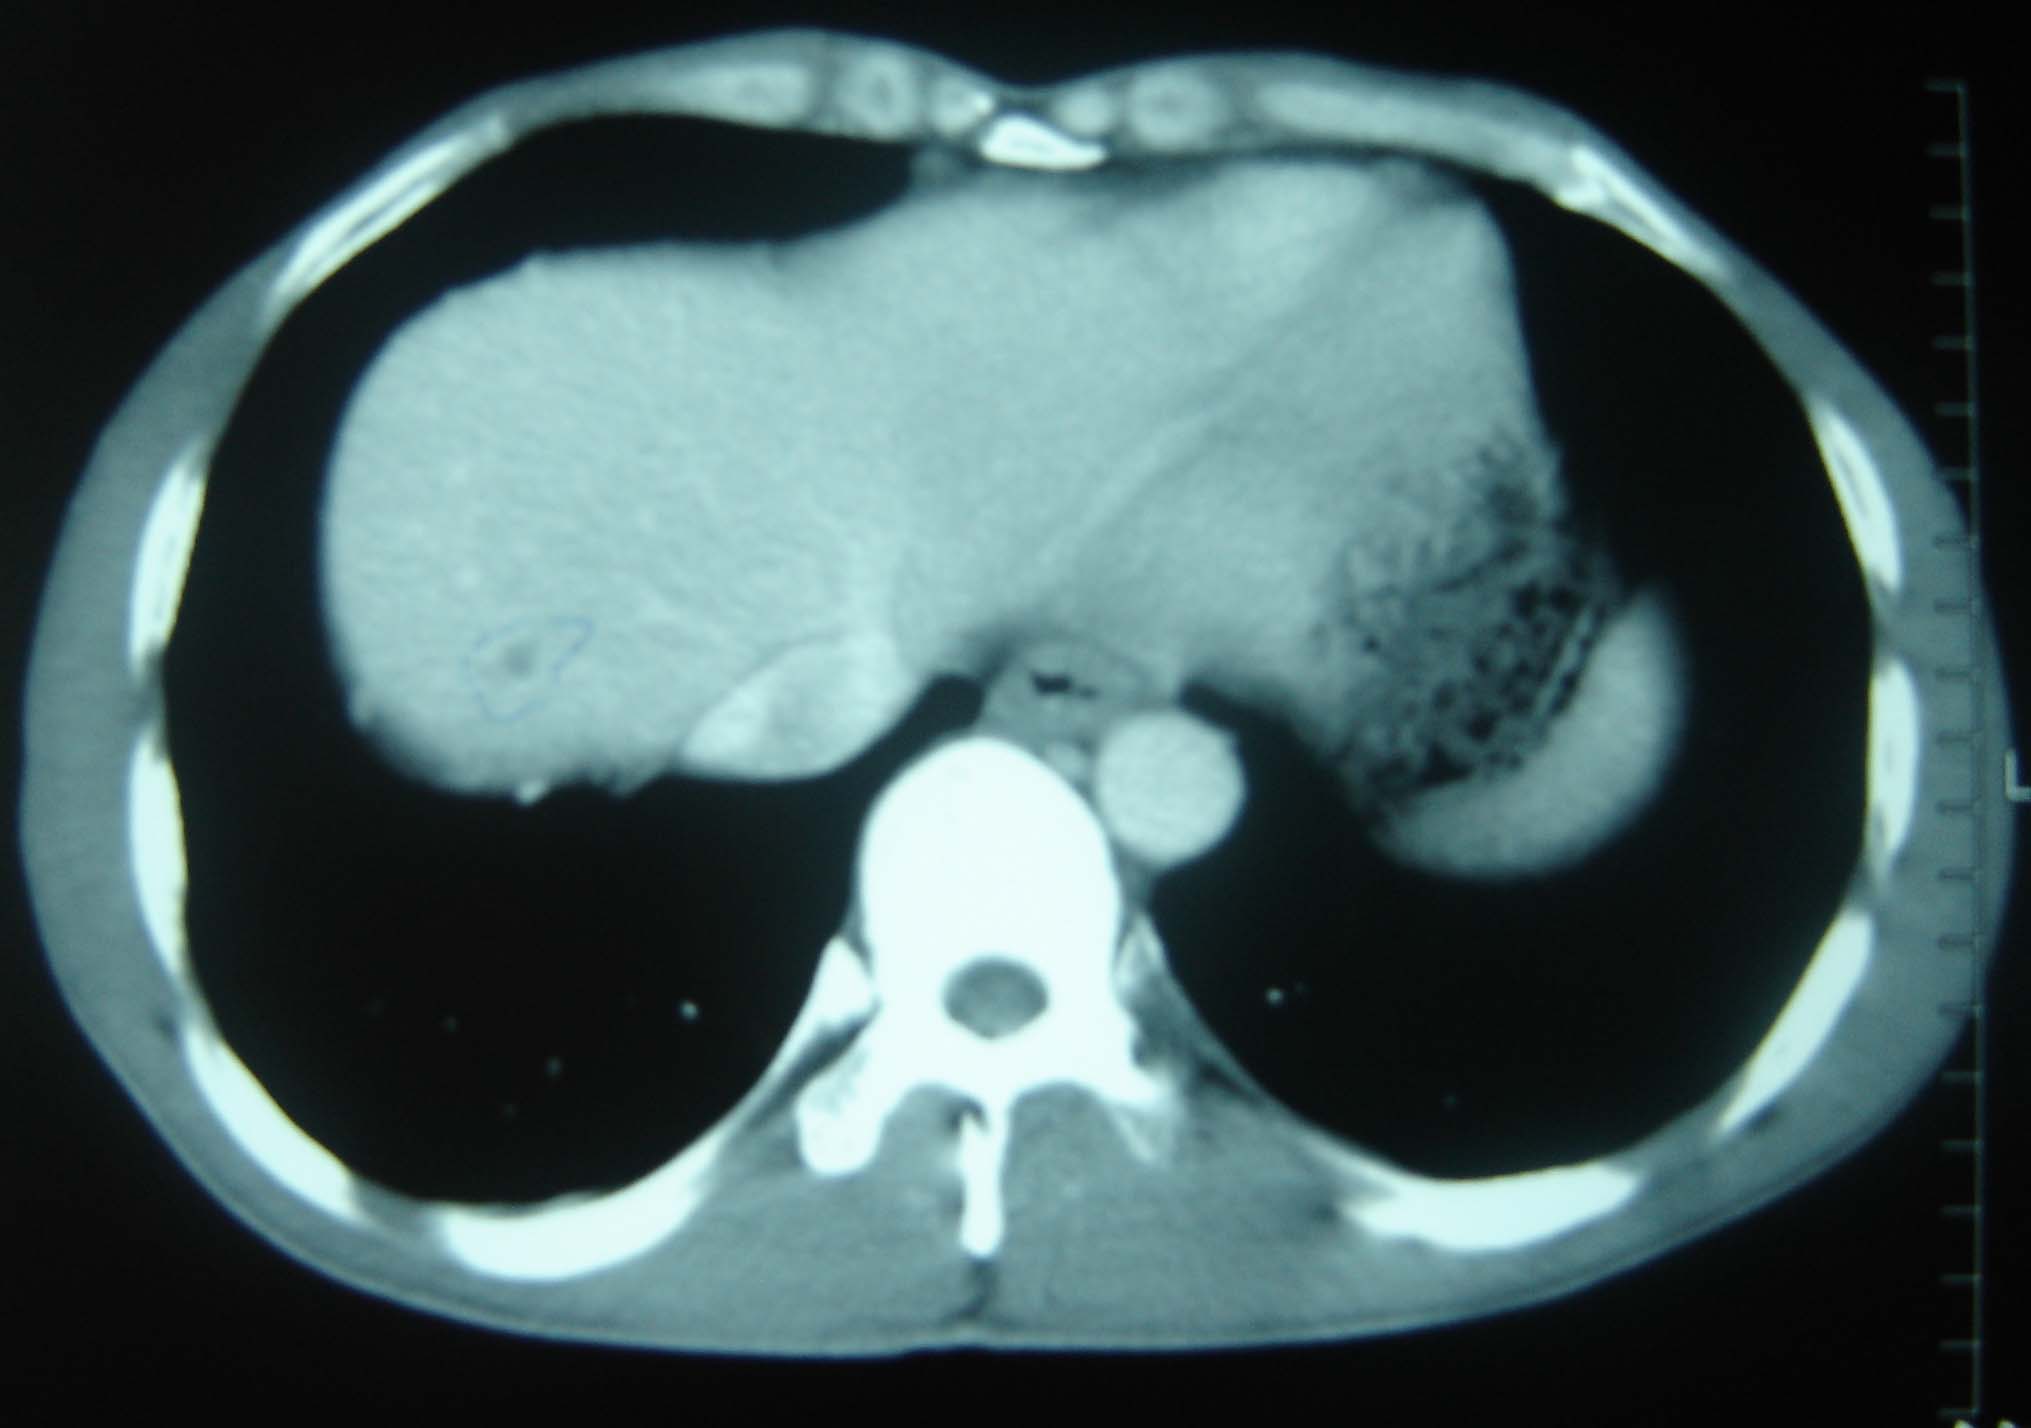

标题: CT25321:两肺多发结节 请会诊 [打印本页]

标题: CT25321:两肺多发结节 请会诊

男 、43岁,咳嗽胸痛,装修工,平时接触粉尘较多,有吸烟史10多年,纤维支气管镜检查未发现异常,胃镜、腹部b超检查亦未发现异常,颈部淋巴结活检未发现肿瘤细胞。

结节病?转移瘤?

1)考虑双肺及胸膜多发性转移瘤。2)肺气肿。

双肺结节病。